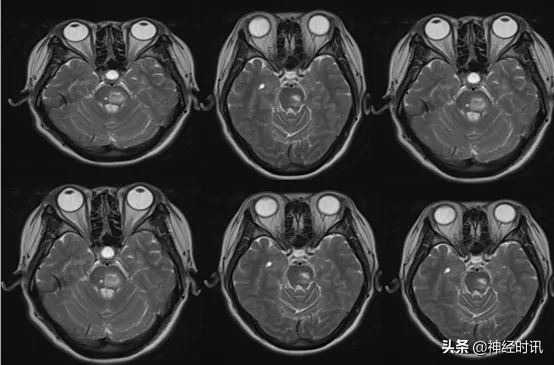

住院9 d,口服脑血疏口服液7 d,患者转入普通病房后复查颅脑MRA+SWI:桥脑出血(亚急性期)

影像结果:桥脑左份可见片状短T1、长T2信号,黑水像呈高信号,周围可见低信号环围绕。左侧基底节可见斑片状等T1、长T2信号,黑水像呈高信号,DWI高b值呈稍高信号,左侧基底节、双侧外囊可见条形长T1、长T2信号,黑水像呈低信号,双侧外囊病变DWI低b值可见低信号环绕。脑灰白质分界清。脑室系统形态、结构及信号未见明显异常。脑沟、脑裂及脑池未见增宽及加深征象。中线结构居中。垂体、视交叉及双侧听神经干未见明显异常。

结果回示:1、桥脑出血(亚急性期),请结合临床。

2、左侧基底节腔梗(急性或亚急性期),请结合临床。

3、左侧基底节陈旧腔梗;双侧外囊陈旧出血。

4、脑MRA:右侧大脑后动脉P1段局限狭窄。

5、脑SWI:双侧基底节、外囊及桥脑异常信号,考虑含铁血黄素沉积。